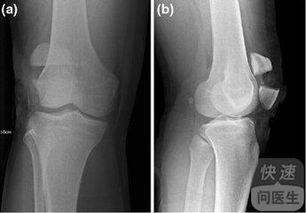

首先,得先了解一下什么是髌骨骨折。髌骨,也就是我们常说的膝盖骨,是人体最大的籽骨,位于膝盖前方。它不仅起到保护膝关节的作用,还能帮助我们在运动时更好地发力。髌骨骨折,顾名思义,就是膝盖骨发生了断裂。